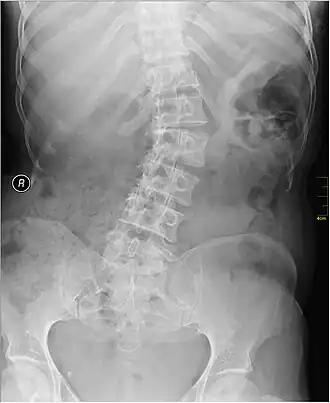

| Radiografia em que se observa deformação lateral da coluna causada por escoliose | |

Escoliose é uma condição médica em que a coluna vertebral da pessoa apresenta uma deformação lateral, formando uma curva.[1] A curva tem geralmente a forma de um "S" ou "C".[1] Em alguns casos o grau de curvatura é estável, enquanto em outros vai aumentando progressivamente com os anos.[2] A escoliose ligeira geralmente não causa problemas, enquanto os casos mais graves podem interferir com a respiração.[2][4] Geralmente não existe dor associada à escoliose.[5]

O diagnóstico é confirmado com radiografia às costas.[1] A escoliose pode ser classificada como estrutural, em que a curvatura é fixa, ou funcional, em que a estrutura da coluna é normal, mas aparenta ser curvada devido a outra condição, como diferença no comprimento das pernas ou espasmos musculares.[1]